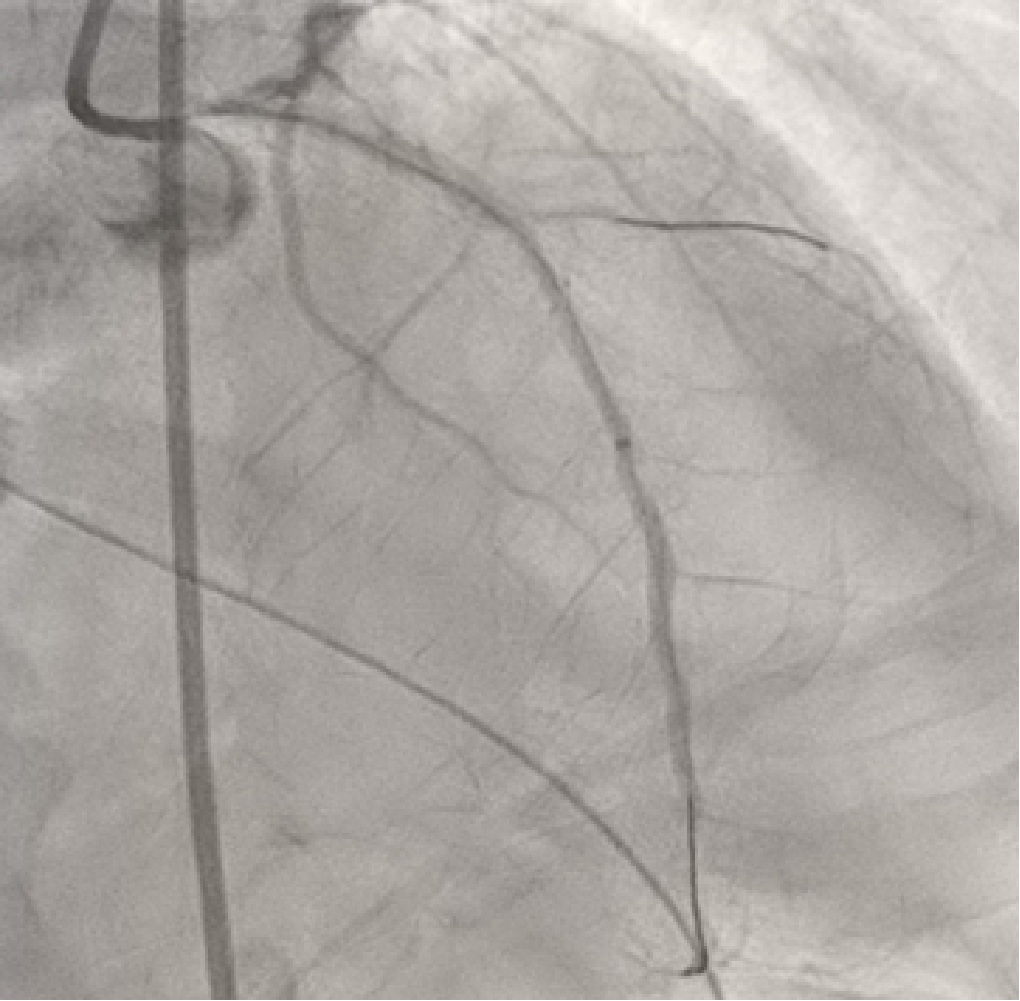

A 3.5x7F ASAHI PB Guide catheter with Sion guidewire was provided for LAD revisualization.After placing the guidewire in LAD, series balloon were provided todilate the stenotic lesions as Figure 1 showed. A 2.5x38 mm stentwas applied to place the distal part lesion of LAD. However, the difficulty to movethe stent to the correct place due to length of the stent and the irregularlumen of proximal part of LAD. 6.0F extension microcatheter was used to assistthe stent moving and implanting. After stenting, the extension microcatheterwas entrapped around middle part of LAD as Figure 2 showed. After pullingbackwards forcedly, the fracture of proximal part of the microcatheter was detectedand previous guidewire was pull out from coronary artery. After rewiring into the distalpart of LAD via the lumen of the fractured microcatheter, 7.0F telescopemicrocatheter with a 2.5x15 mm balloon was applied. The balloon wasmoved in the position 2-3 mm inferior to the fractured microcatheter and proximalpart of telescopemicrocatheter was placed in the ostium of left main coronary artery. After theballoon inflated, the whole sets including the body of the balloon and thetelescope microcatheter were pull backwards. The fractured catheter was movedbackwards with the inflated balloon to enter the telescope microcatheter. Thewhole sets with the fractured catheter were retried from the patientsuccessfully. The retried balloon and fractured catheter were illustrated inFigure 3.